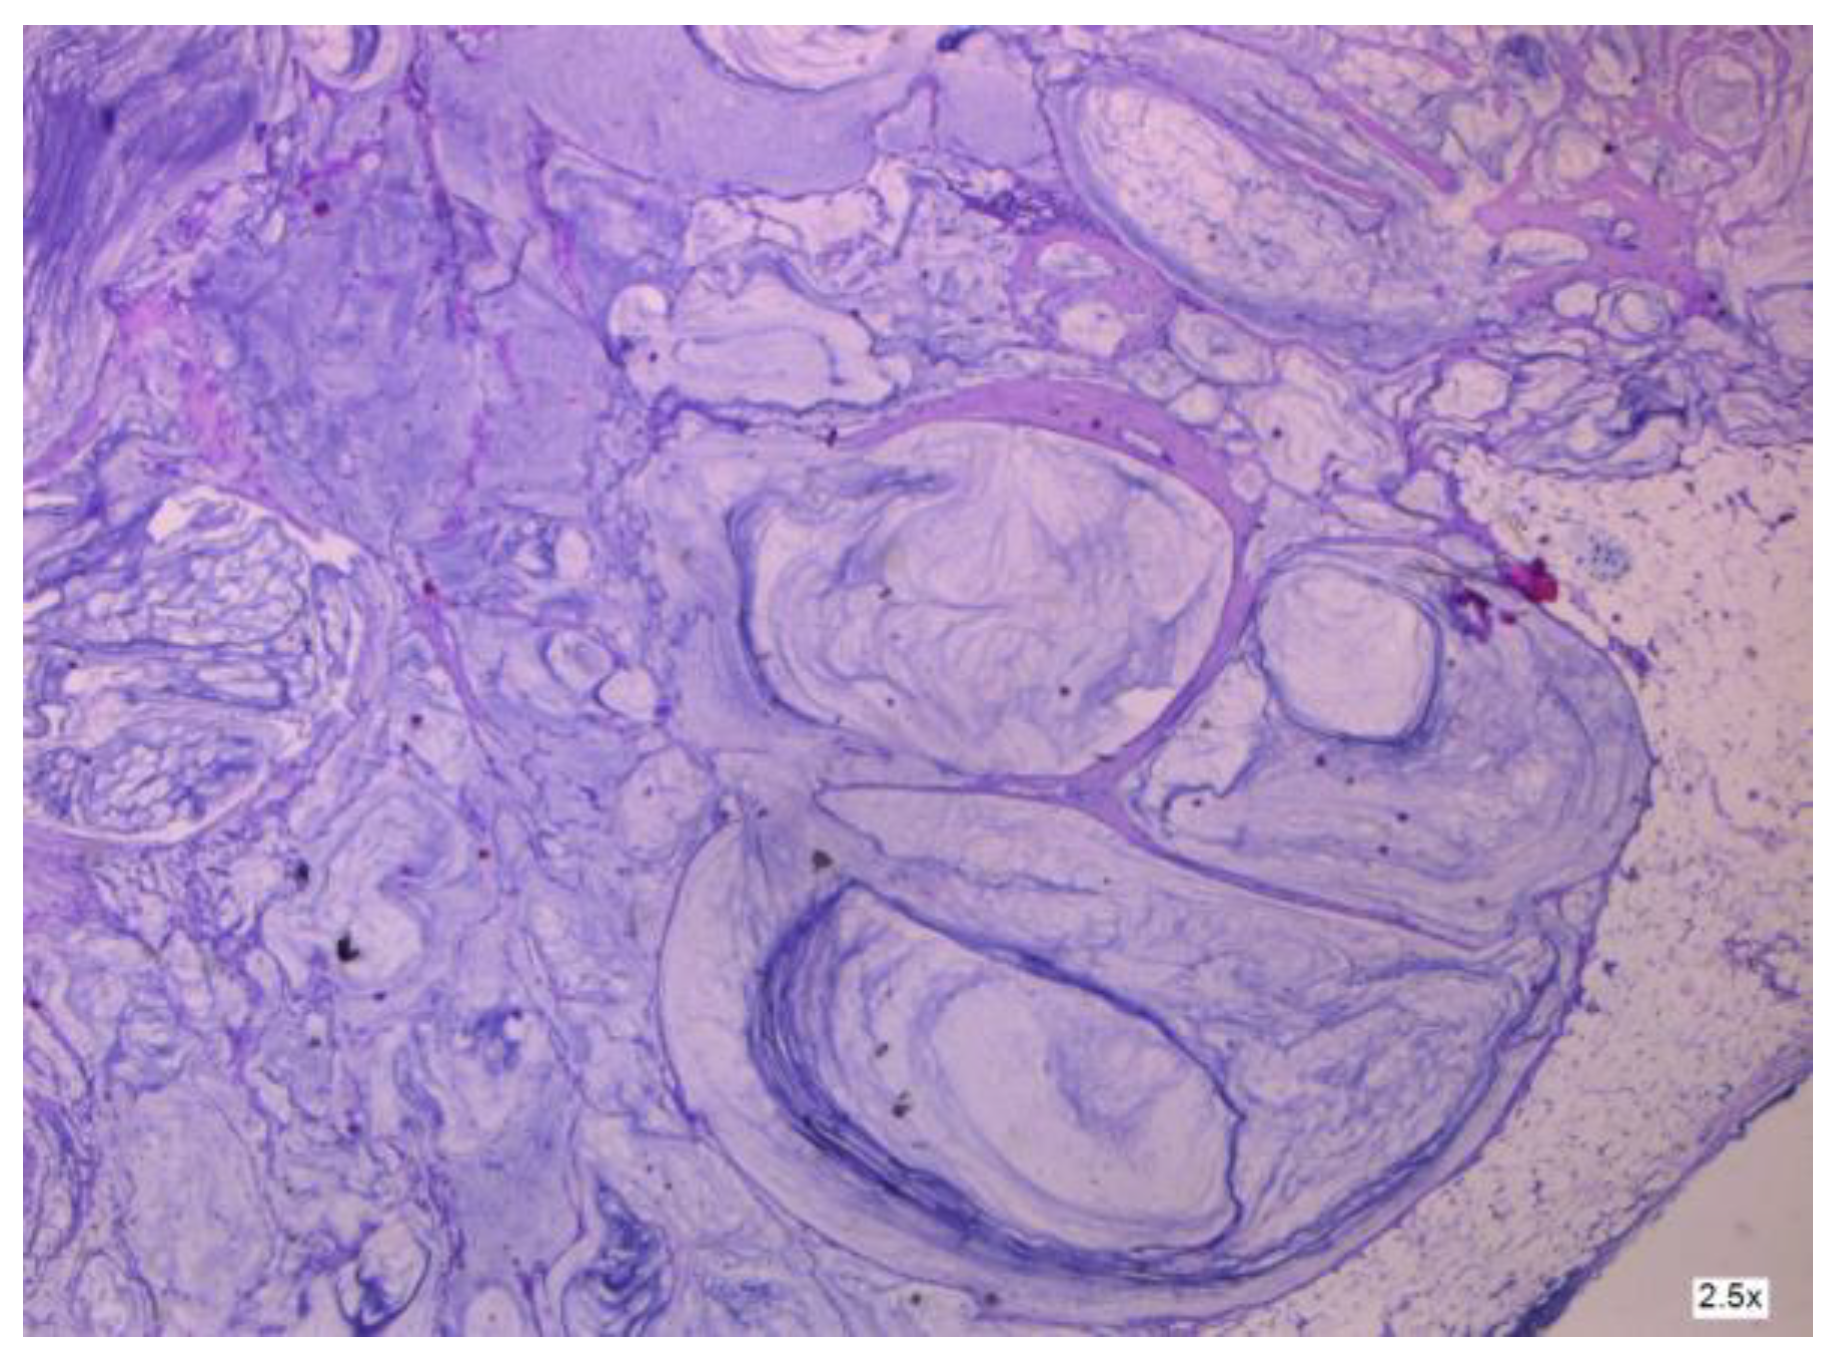

3.2.2. Clinical and Pathology Findings